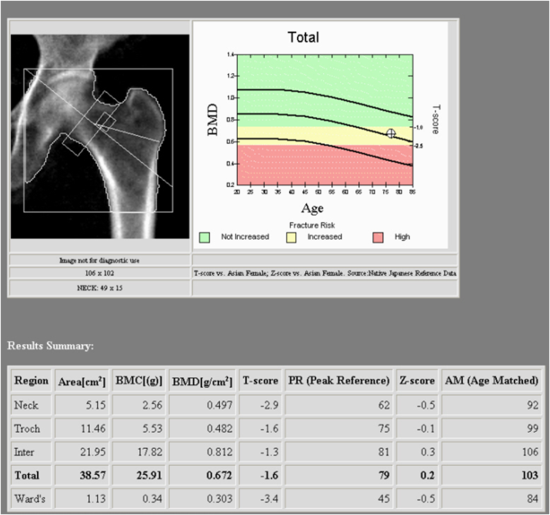

BMD Measurement Area In The Lumbar Spine And Femur A Femoral Neck

Bone Density Results J W NUCLEAR MEDICINE 27 Justin Street Smithfield